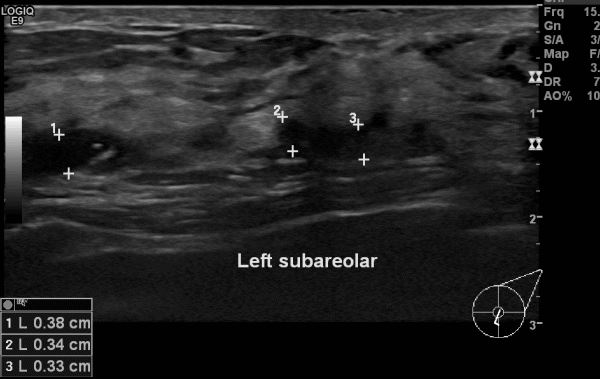

상기환자 50대 여성분으로 좌측 유두 부근 만져지는 멍울 조직검사 시향하여

좌측 침윤성 유관암 진단 되었습니다.